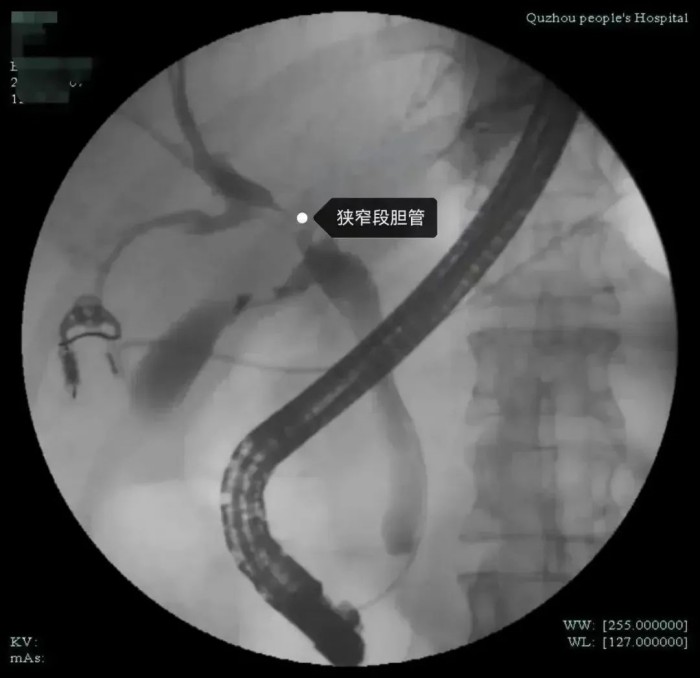

市人民醫(yī)院腫瘤放療科姜忠于主任醫(yī)師認(rèn)為目前不能排除腫瘤可能,需要做進(jìn)一步檢查,以明確診斷。同時(shí)肝膽外科袁磊博士和沈紅波主任醫(yī)師進(jìn)行會(huì)診。經(jīng)全面評(píng)估分析,醫(yī)生發(fā)現(xiàn)患者肝門部膽管狹窄,腫瘤標(biāo)記物不高,肝功能目前正常,狹窄局部無(wú)明顯腫塊,但仍不能排除膽道內(nèi)病變可能,決定對(duì)張女士行ERCP(內(nèi)鏡下逆行膽胰管造影術(shù))檢查,同時(shí)在ERCP下行經(jīng)口膽道鏡檢查。

經(jīng)過(guò)與張女士及其家屬詳細(xì)溝通后,在麻醉科、內(nèi)鏡中心的全力配合下,沈紅波為張女士實(shí)施了無(wú)痛經(jīng)口電子膽道鏡檢查。術(shù)中,沈紅波發(fā)現(xiàn)膽管狹窄處蒼白僵硬,黏膜表面雖然無(wú)明顯新生物,但仍不能排除膽管內(nèi)腫瘤的可能性。因此,他在膽道鏡探查的同時(shí)也取活檢和細(xì)胞刷檢,來(lái)鑒別是否是腫瘤。很快,術(shù)后活檢結(jié)果出來(lái)了,病理切片提示為惡性腫瘤。

經(jīng)口膽道鏡到底是一種什么樣的內(nèi)鏡呢?據(jù)介紹,經(jīng)口電子膽道鏡技術(shù)俗稱子母鏡,就是將一個(gè)更小、更精細(xì)的子鏡,經(jīng)過(guò)十二指腸鏡(母鏡)的孔道深入到膽管、胰管內(nèi),直視觀察膽管、胰管內(nèi)病變,為膽胰管疾病診療提供直視化、高清化、精確化的解決方案。

沈紅波介紹,我院率先在衢州地區(qū)引進(jìn)了經(jīng)口電子膽道鏡系統(tǒng),該設(shè)備可以進(jìn)入膽胰管內(nèi)進(jìn)行直視下的檢查,有利于早期發(fā)現(xiàn)病灶,精準(zhǔn)取活檢。直視電子膽道鏡的內(nèi)鏡直徑為9Fr(3毫米),可以進(jìn)入肝內(nèi)的3-4級(jí)膽管及胰管內(nèi)。既往傳統(tǒng)的十二指腸鏡無(wú)法進(jìn)入膽管內(nèi)進(jìn)行直視檢查治療,膽管內(nèi)結(jié)石等病變只能通過(guò)透視下的模糊影像辨認(rèn)。以前要想進(jìn)行膽道內(nèi)直視檢查,需借助腹腔鏡或經(jīng)皮經(jīng)肝膽道穿刺建立通道后才能將膽道鏡送入膽管,創(chuàng)傷大。但直視的電子膽道鏡可以通過(guò)十二指腸鏡鉗道內(nèi)進(jìn)入到膽管、胰管內(nèi)進(jìn)行直視下觀察病變、取活檢、碎石等治療,能夠早期發(fā)現(xiàn)微小病變,特別是對(duì)于膽胰腫瘤的早發(fā)現(xiàn)、早治療具有很高的臨床價(jià)值。